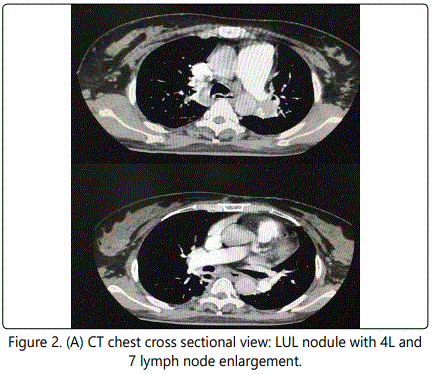

A 44-year-old Thai female, who was diagnosed alcoholic cirrhosis, Child-Pugh score of 7 for 2 years, presented with clinical of high grade fever, abdominal pain and abdominal distension. The abdominal paracentesis was performed and diagnosed spontaneous bacterial peritonitis (SBP). She was given intravenous cefotaxime for SBP treatment. During work up for cause of fever, the chest radiograph (CXR) was done and showed left upper lung nodule closed to aortic knob and the decrement of left lung volume which deferred for left upper lobe atelectasis (Figure 1A). She had no history of respiratory symptoms and no history of tuberculosis or tuberculosis exposure. She is non-smoker. Her past medical history was not significant except her liver condition which was treated with low dose spironolactone 50 mg per day. Her family history was noncontributory. Her physical examination was slightly decrease breath sound at left upper lung. Laboratory studies showed leukocytosis of 17,800 cells/ul. Sputum and blood culture were negative. Sputum smear acid fast bacilli for three days were negative. Sputum culture for tuberculosis was negative. Computerized tomography (CT) of the chest was performed and revealed a 2 centimeters enhancing intrapulmonary nodule involved left apicoposterior bronchus with intraluminal extension caused sub segmental atelectasis with fluid filled bronchi distal to lesion (Figure 1B). There were left paratracheal (4L) and subcarina (7) lymph nodes enlargement, 1 and 1.4 cm, respectively (Figure 2A and B). No evidence of metastatic disease was seen.